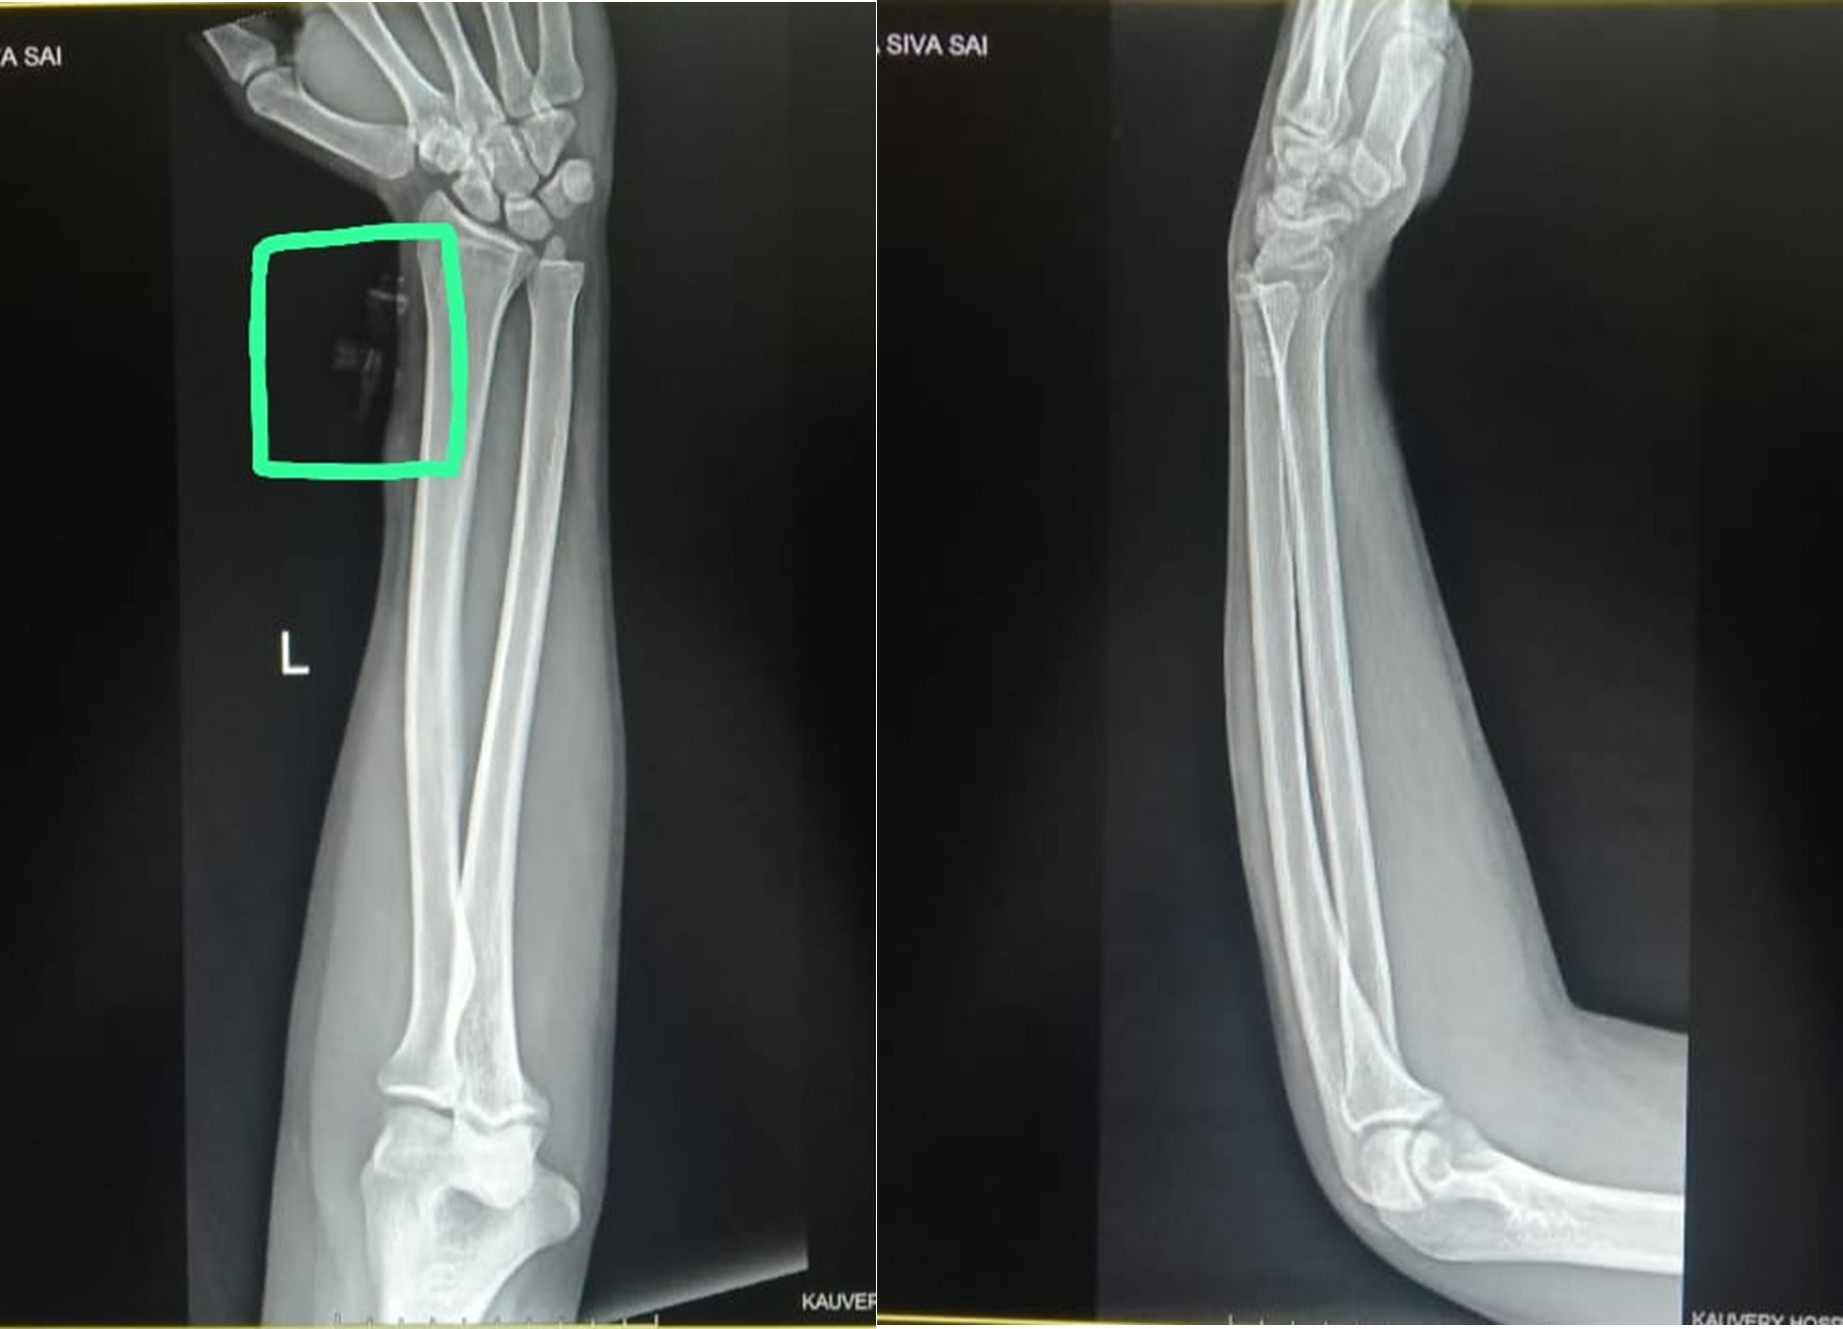

Radiology: An urgent Upper Limb (UL) Doppler Ultrasound was requested to localize the retained foreign body and assess vascular integrity. Although a separate formal Doppler report is not available in the documentation, operative notes confirm that the migration and location of the IV cannula tip were verified using ultrasound guidance.

X-ray

Under aseptic precautions, a skin incision was made over the presumed site. Utilizing ultrasound (USG) guidance, the cephalic vein was identified, and the migration of the IV cannula tip was confirmed. The vein was exposed, and a venotomy (incision into the vein) was performed. The cannula fragment was successfully removed. No intraoperative complications were documented. Post-removal confirmation was achieved via USG to reconfirm the absence of residual fragments. The venotomy and wound were closed.